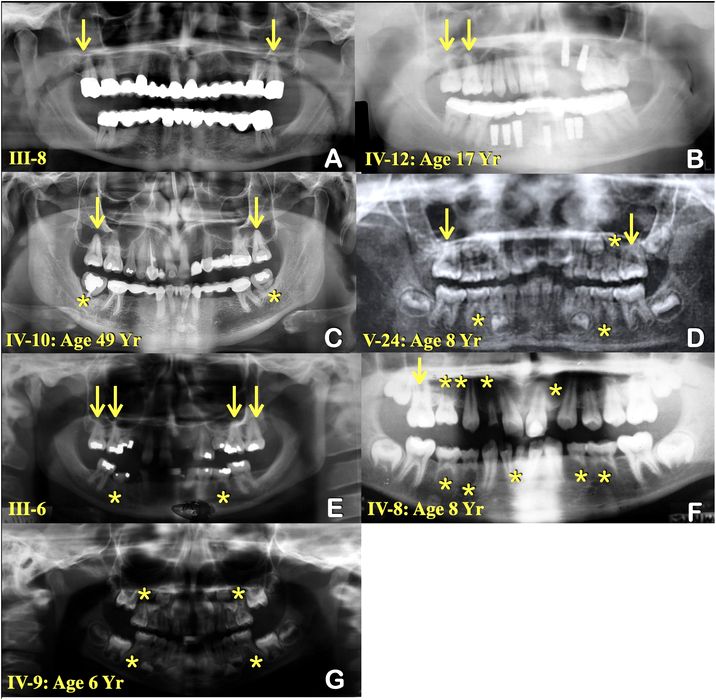

A fost descoperită cauza pentru o mutație genetică misterioasă

Un doctor a descoperit mutația genetică din spatele misterioasei lipse de dinți a familiei sale. Pacientul este John Graham, profesor de genetică medicală și pediatrie la Cedars-Sinai Medical Center din Los Angeles (SUA). Majoritatea nou-născuților […]